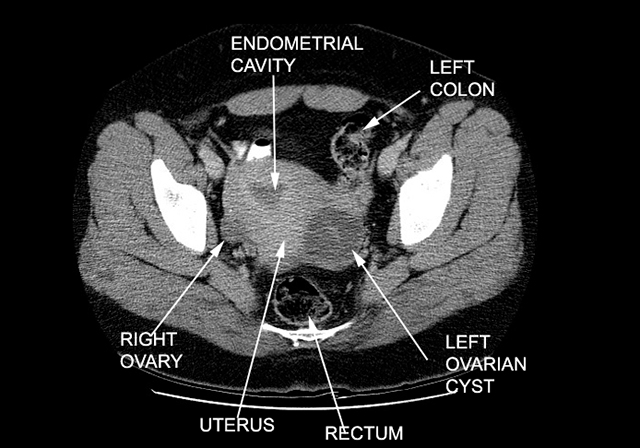

Ovarian Cyst

Case 1

Patient is a 37 yr/o G3P2012 who comes to the ER complaining of severe abdominal pain. Patient has had a similar pain in the past. Patient has regular periods, which come every 28-30 days. Her LMP was 2 weeks ago. She is afebrile. On physical exam, she has right lower quadrant tenderness, with no rebound or guarding. Patient has no cervical discharge, no cervical motion tenderness, but does have right adenxal tenderness.

CT pelvis . Left ovarian cyst. |